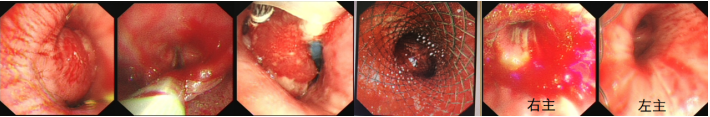

良性中心气道狭窄分为结构性和动力性(6种类型),结构性狭窄包括:管腔内生长(1型),外源性压迫(2型),瘢痕孪缩(3型),扭曲变形(4型);动力性狭窄包括:气道膜部向内膨出(5型),气道软化(6型)。对于动力性狭窄,应考虑用力呼气时的状态,通过操作者的判断,定出最合适、最接近的狭窄程度。治疗方法的制定不仅与气道狭窄程度和长度有关,还与是否存在狭窄过渡段有关。狭窄长度的计算应包括过渡区域。良性气道狭窄形态学分类的诊断方法应通过支气管镜所见及放射学检查来确定。每一个狭窄都可以用4个数字来表示,分别代表部位、类型、狭窄程度、狭窄长度。如:1344代表声门下瘢痕性挛缩性狭窄、狭窄程度>75%、狭窄长度>5 cm,这是一种非常难以处理的良性气道狭窄;2311代表气管瘢痕性蹼状网眼狭窄、狭窄程度<25%、狭窄长度<1 cm,这是一种比较容易处理的良性气道狭窄。热消融技术(APC、电凝、激光)是治疗增生性气道腔内病变(如良性肿瘤和单纯肉芽)的简单、快速的方法。但在治疗瘢痕狭窄病变时,其本身可对气道造成更重、更大范围的损伤,引起更为严重的肉芽组织增生和瘢痕形成,从而导致复发率高,且治疗次数的增加可导致狭窄病变范围增大并最终破坏软骨,导致气道塌陷,使患者彻底失去治愈的机会。电凝和APC仅适合管腔内生长的1型良性中心气道狭窄,并不适合其他类型良性中心气道狭窄的治疗。即便如此,基底部的处理也应避免使用此类治疗方法。针形电刀与气道黏膜接触面极小,不会造成损伤面扩大,瘢痕性气道狭窄的治疗宜选用针形电刀进行切割、松解。因激光也有切割的作用,因此也可选用激光治疗,钬激光、铥激光控制烧灼深度最浅可达0.4 mm,因此更适合良性瘢痕增生性气道狭窄的治疗。冷冻治疗分为冷冻切除(简称冻切,cryoextraction)及冷冻消融(简称冻融,cryoablation)。对于腔内生长的病变可采用冻切治疗,由于容易出血,其安全性不如热消融技术。对于瘢痕病变,冻切技术无法实施,则采用冻融治疗,冻融治疗不促进肉芽组织增生。与热消融相比,冷冻不易导致软骨损伤。通常在热消融治疗接近气道壁时或球囊扩张后采用冻融治疗处理剩余病变,有利于减轻瘢痕再狭窄发生的速度与程度。严重气道狭窄在开通气道前不要使用冻融,因其可引起气道水肿,加重气道狭窄,从而导致窒息。因此,冻融治疗后肺部体征监测及气管镜复查十分重要。机械扩张技术包括球囊扩张和硬质支气管镜扩张,并发症有气道撕裂、再狭窄、出血。(1)球囊扩张:是治疗瘢痕性气道狭窄最主要的技术,其优势是患者治疗后无明显的狭窄段延长,狭窄复发时再狭窄的程度比热消融治疗后轻得多,有利于维持气道复张的疗效。对气管黏膜损伤小,可以在软镜下应用,但需要中断通气。对于挛缩、韧性较强的瘢痕,可先用针形电刀进行切割以松解瘢痕;避免直接暴力球囊扩张,导致气道膜部的撕裂伤。(2)硬质支气管镜扩张:其优势是扩张时不需要中断通气,安全性更好。针对瘢痕肉芽组织增生导致介入治疗后的气道再狭窄,可采用气道狭窄部位局部应用药物的方法抑制瘢痕肉芽组织增生。介入治疗后气道再狭窄可选择的治疗药物有:糖皮质激素、丝裂霉素C、曲尼斯特、紫杉醇等。通过直接植入放射性物质(最常用铱-192)或经过可弯曲支气管镜近距离照射气道瘢痕肉芽组织,促使成纤维细胞凋亡。气道支架置入首选硅酮支架,禁用金属裸支架。支架治疗应作为良性气道狭窄最后选择的治疗技术,启动气道支架治疗的指征:①应用前述各种治疗方法疗效不佳,不能维持气道通畅;②在确定外科手术前临时放置;③外压性气道狭窄;④气道软化、塌陷且无法或不准备行外科手术治疗。病例1:17岁,女性,骨折术后肺炎插管,拔管后(2月14日)气道明显狭窄(图3)。2月15日评估:HR 113次/min,R 24次/min,静息下SpO2 97%(FiO2 50%),咳嗽及说话后喘鸣,有阵发性血氧下降。会诊后拟行急诊介入治疗。2月15日无痛气管镜示:声门下腔黄色及乳白色膜状坏死物,气管上段大量黄色坏死物并管腔重度阻塞,仅见小孔,以冷冻法清除坏死物后管腔通畅(图4)。术后气促明显改善,无需吸氧。病例2:77岁,女性,呼吸困难2个月,加重3天,于2023年12月2日入院(2023年9月气管插管,插管后20余天后拔管)。入院当天查体:HR 125次/min,R 30次/min,静息下SpO2 96%(高流量FiO2 30%),PaCO2 56 mmHg。患者术前影像如图5所示。12月3日查体:HR 140次/min,R 35次/min,BP 190/90 mmHg,SpO2 68%~75%(FiO2 100%),躁动不安,急查血气分析:PaCO2 89 mmHg。紧急床旁无创通气支持下气管镜:气管上段狭窄80%以上,较多黄白黏稠分泌物在狭窄口随呼吸摆动,予抽吸后SpO2升至98%,见狭窄处直径约3 mm,外径5.2 mm,软镜无法进入,遂置入导丝,10#球囊扩张多次,狭窄部位增宽,外径4 mm气管镜引导6.0号气管导管经口插管成功(图6)。插管后患者HR 98次/min,复查血气分析示PaCO2 41 mmHg,氧合指数300 mmHg以上。12月4日气管镜示:右鼻旁路进镜,缓慢退气管导管至声门,距声门3 cm处狭窄,直径7 mm,予12#球囊扩张1 min,2次,未见出血,扩张后直径约12 mm,地塞米松局部保留,气管导管复位(图7)。12月5日拔除气管导管。12月6日气管镜示:气管上段瘢痕狭窄(管径10~12 mm),少许膜状坏死、未见肉芽,予以清除坏死物,7点、11点冻融,术毕注入地塞米松5 mg(图8)。12月13日气管镜示:气管上段瘢痕狭窄(管径12 mm左右),少许膜状坏死、未见肉芽,予以清除坏死物,7点、11点冻融,术毕注入地塞米松5 mg(图9)。

图9 气管镜下操作(2023-12-13)